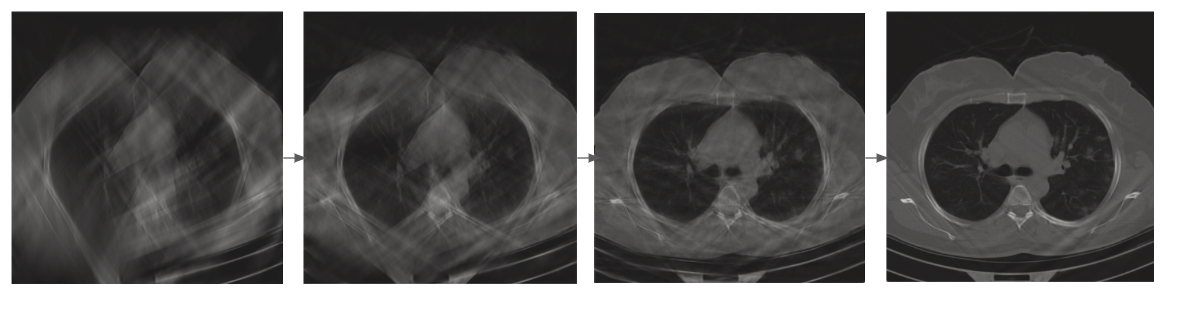

Изображение иллюстрирует зависимость качества КТ-снимка легких от количества проекций: чем больше проекций – тем лучше изображение

“Представим, что с помощью стандартного протокола в ходе томографического измерения от объекта регистрируются 360 проекций. Мы же предлагаем регистрировать сначала пять проекций, потом, если качество изображения недостаточно хорошее, еще пять и так далее. Возникает вопрос: зачем регистрировать дополнительные проекции и тратить на это время, если качество изображение уже является достаточным”, – рассказывает один из авторов изобретения, старший научный сотрудник-программист Smart Engines кандидат технических наук Константин Булатов.